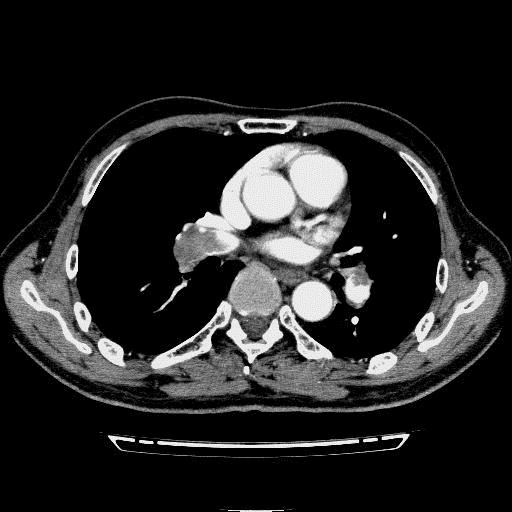

问题 病历摘要: 患者女性,83岁,活动后气促10天,伴心悸、咳嗽,咳少许白粘痰,感左侧胸痛,呈压榨样,与呼吸有关,但无放射痛,并发热,体温最高37.9℃,无明显规律性,无咯血、畏寒等。既往有系统性红斑狼疮病史,有吸烟史20年,已经戒烟20年。1月前始自觉双下肢易疲劳,但活动不受限。体查:T37.7℃,左肺可闻及啸鸣音和少许细湿啰音,心率123bpm,律齐,P2>A2,未闻及杂音。双下肢无水肿。 急诊最好应先行哪些检查?

选项 A.血常规 B.血浆D-二聚体 C.凝血三项 D.动脉血气分析 E.胸部X线检查 F.胸部B超 G.心脏彩超 H.胸部CT平扫+增强 I.心电图

答案 ABCDEI